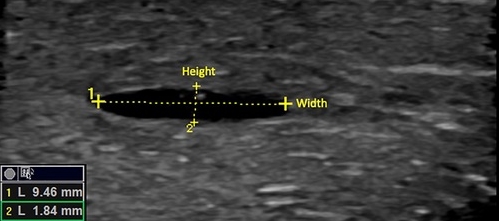

《PMID:38769647》研究在超音波影像引導下測試,不同HA填充劑注射到雞胸組織中,以模擬人體應用。注射後立即測量,HA團塊的平均寬度和高度分別為15.37mm、4.00mm。打降解酶一小時後,寬度和高度分別縮小為11.36mm、2.53mm。24小時後降解再度測量,總體積減少量達81.7%。